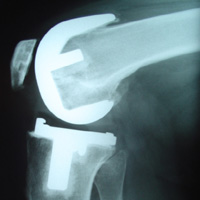

یک محقق سوئدی هشدار می دهد که تعداد تعویض زانو افزایش پیدا کرده است زیرا عفونت زانو زیاد شده است.

محققی به نام «آنا استفانستودیر» از دانشگاه لوند می گوید:تعویض زانو 9% در سال های اخیر افزایش پیدا کرده است.

بنا بر این اگر 1 درصد یه 2 درصد از عملیات منجر به عفونتهای باکتریایی شود،پس نیاز به تجدید نظر و عمل دو باره وجو دارد.

«استفانستودیر » توضیح می دهد:که اغلب این نسخه ها شامل دو جراحی است،اولی درمان موقت که فرد بیمار با آنتی بیوتیک چند هفته تحت درمان است.سپس عمل بیشتر برای وارد کردن پروتز جدید.

در بعضی موارد هنگامی که نمی توان پروتز های جدید قرار داد بیمار بر روی صندلی چرخ دار می نشیند و خیلی به ندرت این عفونت باعث قطع عضو می شود.

محققان تقریبا 480 مورد از جایگزینی زانو در یال 1986 تا 2000 بررسی کردند.